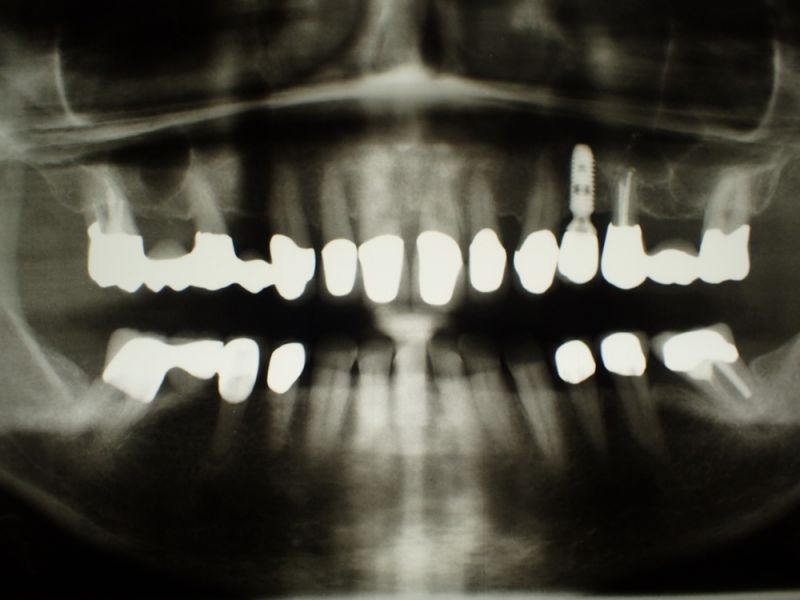

Hier entsteht jetzt ein spannendes Projekt, denn die funktionstherapeutische Totalrekonstruktion der Patientin ist seit nunmehr 25 Jahren in Funktion und gerade in den vergangenen Coronajahren haben sich an wichtigen Pfeilerzähnen Verschlechterungen eingestellt, die die Prognose der Stützpfeiler für eine neuerliche Rekonstruktion der inzwischen mitte-60-jährigen Patientin deutlich reduziert haben.

Also, wird es darum gehen in den Stützzonen in einer geschickten Ausnutzunt noch vorhandener Zähne und zur Implantainsertion geeigneter Lücken eine neue Totalrekonstruktion vorzubereiten, mit dem Ziel die Patientin in den kommenden Jahren nochmals so zu versorgen, dass eine neue funktionstherapeutische Totalrekonstruktion sie dann bis weit ans Lebensende führen könnte.